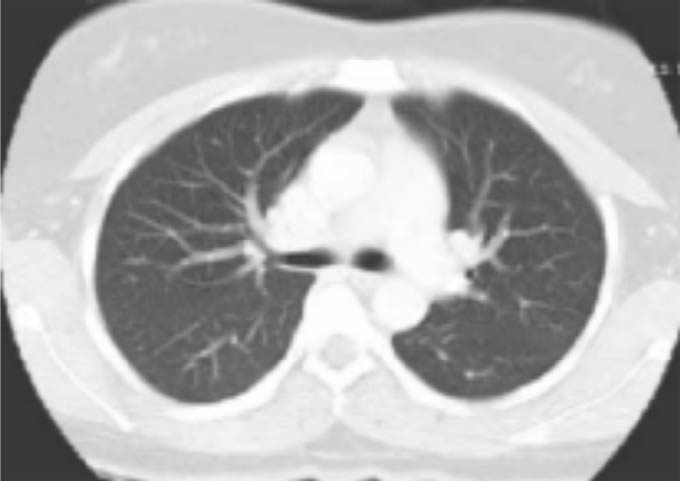

Figura 7: TAC de tórax de Pulmón Sano

La primera es una tomografía normal, se ve un color negro normal con líneas blancas que son las arterias, y el centro es el corazón. (figura 7)